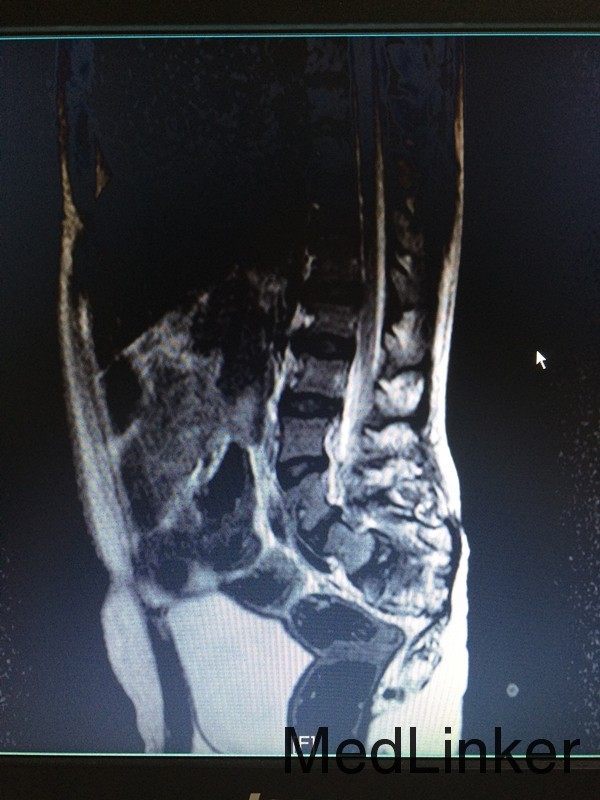

主诉:行走不稳10余年 病史:患者12岁男性,出生后即发现骶尾部包块,行走不稳,间有小便失禁,大便正常,未予特殊处理。近期患者出现行走不稳较前加重,遂来我院就诊,拟议“脊髓栓系综合征”收入院

查体:腰椎后突畸形,双小腿肌肉萎缩,双足内翻畸形,双侧踇指伸指无力。 辅助检查:行脊椎MR检查提示:骶椎发育畸形,脊髓圆锥低位,考虑脊髓栓系综合症,神经源性膀胱。

诊断:脊髓栓系综合症 治疗:神经外科联合骨科在全麻下行脊髓栓系松解、椎板修补术,术后予对症支持治疗。